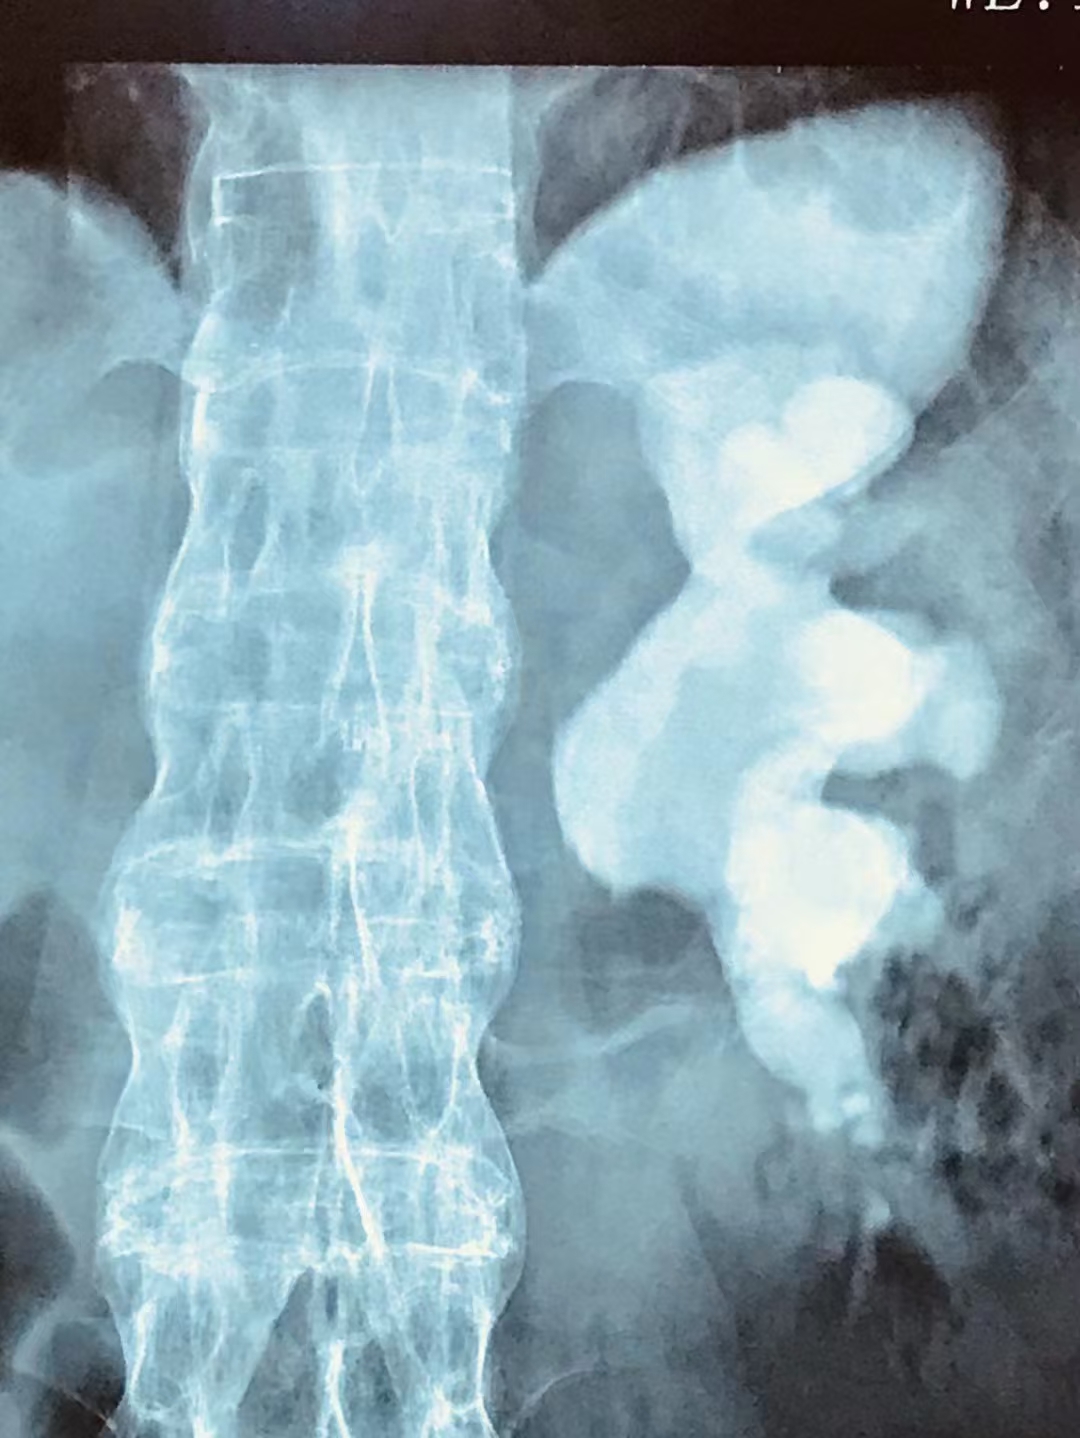

▲铸型结石

像张师傅这种结石体积、个头比较大的铸型结石,具有分布繁琐、复发率高、手术难度高且取石困难等特点,可能需要多次手术才能处理干净,住院周期也更长。